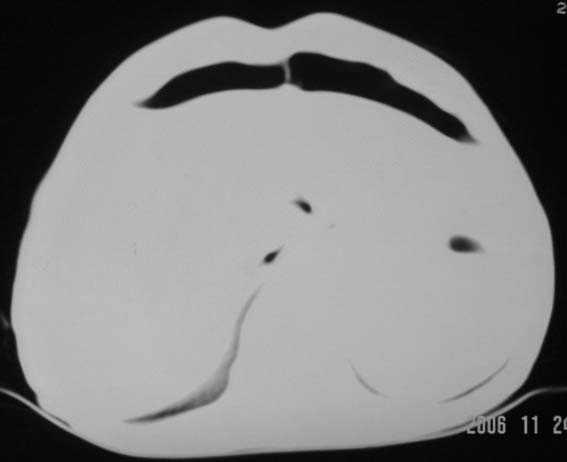

仰卧位见:肝前间隙及肝脾间隙内可见新月形气体密度影,边缘清楚,侧卧位见气体随体位改变而移动,ct值约-929hu。膈下、肝下间隙及部分肠间隙可见液性密度影。考虑:1、上腹部空腔脏器穿孔,以胃穿孔可能性大。2、少量腹水。

仰卧位见:肝前间隙及肝脾间隙内可见新月形气体密度影,边缘清楚,侧卧位见气体随体位改变而移动,ct值约-929hu。膈下、肝下间隙及部分肠间隙可见液性密度影。考虑:1、上腹部空腔脏器穿孔,结合临床,首先考虑胃穿孔可能性大。2、少量腹水

支持消化道空腔脏器穿孔(腹腔内大量游离气体影,小网膜囊内亦见气体影),少量腹水。